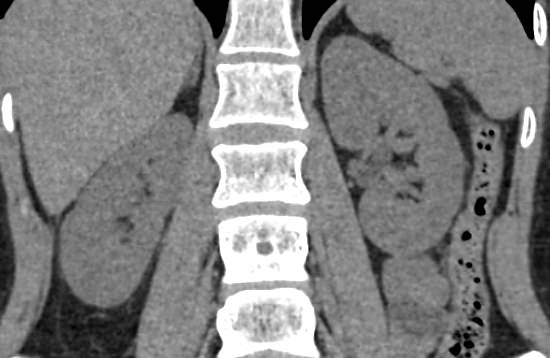

Мультиспиральная компьютерная томография почек и мочевыводящих путей является высокоинформативным методом исследования, основанном на использовании воздействия рентгеновских лучей на органы и ткани человека. Методика предусматривает послойное сканирование области почек, мочевыводящих путей и получение снимков исследуемой области в мельчайших подробностях.

Для улучшения визуализации патологических очагов в некоторых случаях дополнительно применяется контрастное усиление. Для этого пациенту внутривенно вводится йодсодержащее контрастное вещество, которое накапливается в патологически измененных участках и вызывает их яркое контрастирование на фоне здоровых тканей.

МСКТ почек и мочевыводящих путей с контрастированием позволяет выявить опухолевые образования на ранних стадиях, отличить доброкачественную опухоль от злокачественной, определить размеры опухоли, точную локализацию и степень распространения в окружающие ткани. Компьютерная томография почек с внутривенным болюсным контрастированием необходима для определения тактики лечения и объема оперативного вмешательства.